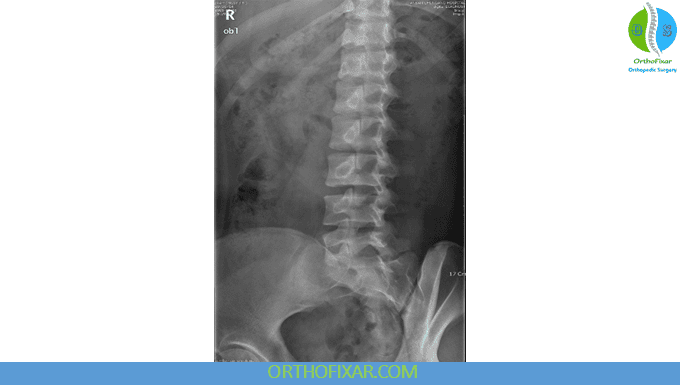

Oblique View

The oblique lumbar X-ray helps detect pars interarticularis defects.

- A “Scottie dog with a collar” appearance indicates spondylolysis.

- A “decapitated Scottie dog” appearance indicates spondylolisthesis.